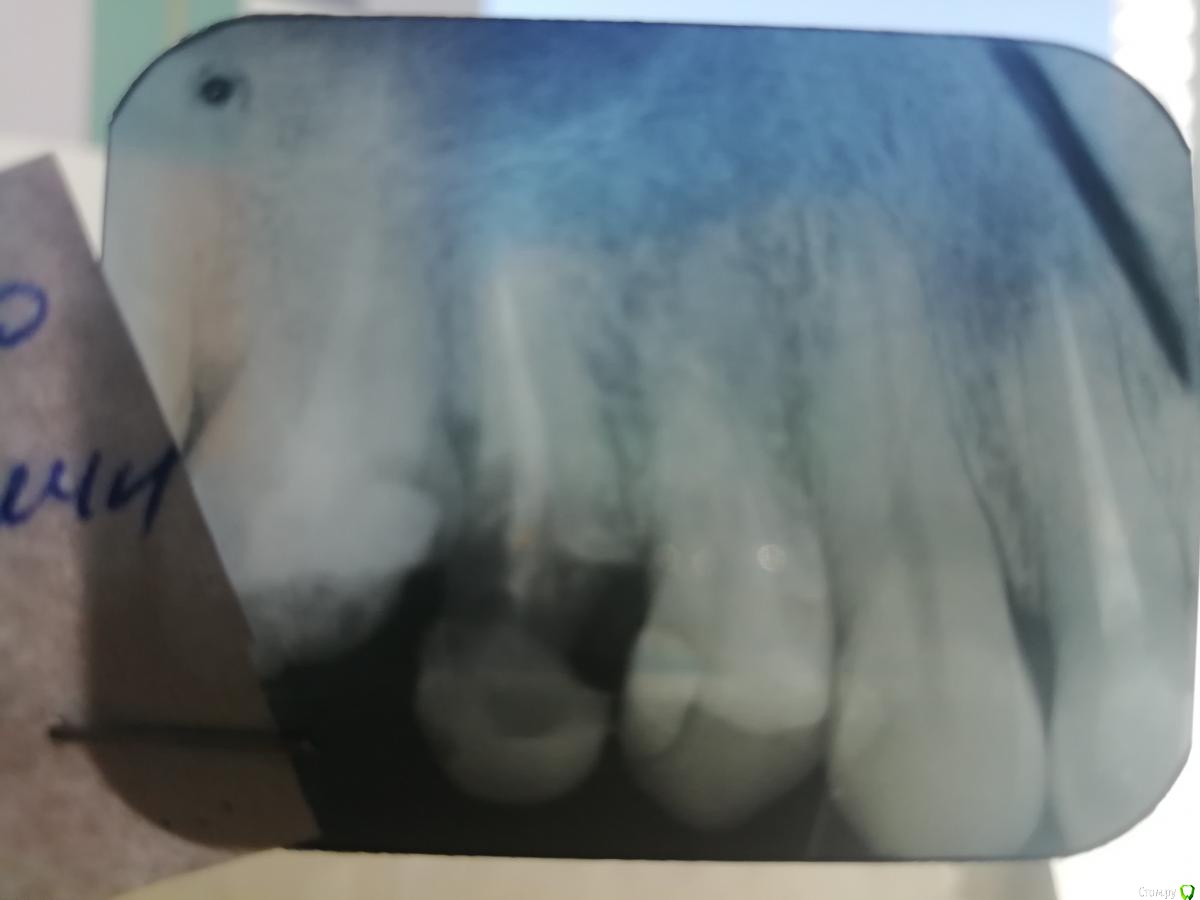

Nail47 Опубликовано 26 июля, 2020 Поделиться Опубликовано 26 июля, 2020 Всем здравствуйте! 14 зуб я как понял, либо пятый по счету на верхней челюсти справа.Давно уже леченный (без нерва), недавно развалился, выпала большая пломба, в итоге по факту просто одна внешняя стенка осталась. По снимку (приложил), один врач говорит удалять однозначно, корень глубоко поврежден. Другой вроде как берется лечить под коронку. Хотелось бы больше мнений получить, стоит спасать или проще под протез пускать? Ссылка на комментарий